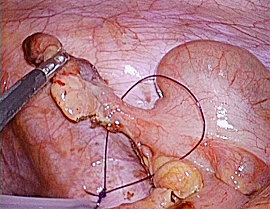

[急性虫垂炎] 手術:腹腔鏡下虫垂切除術

急性腹症のため救急受診。精査の結果、急性虫垂炎および限局性腹膜炎と診断。緊急手術(腹腔鏡下虫垂切除術)を施行した。病理診断結果は急性虫垂炎であった。

手術画像